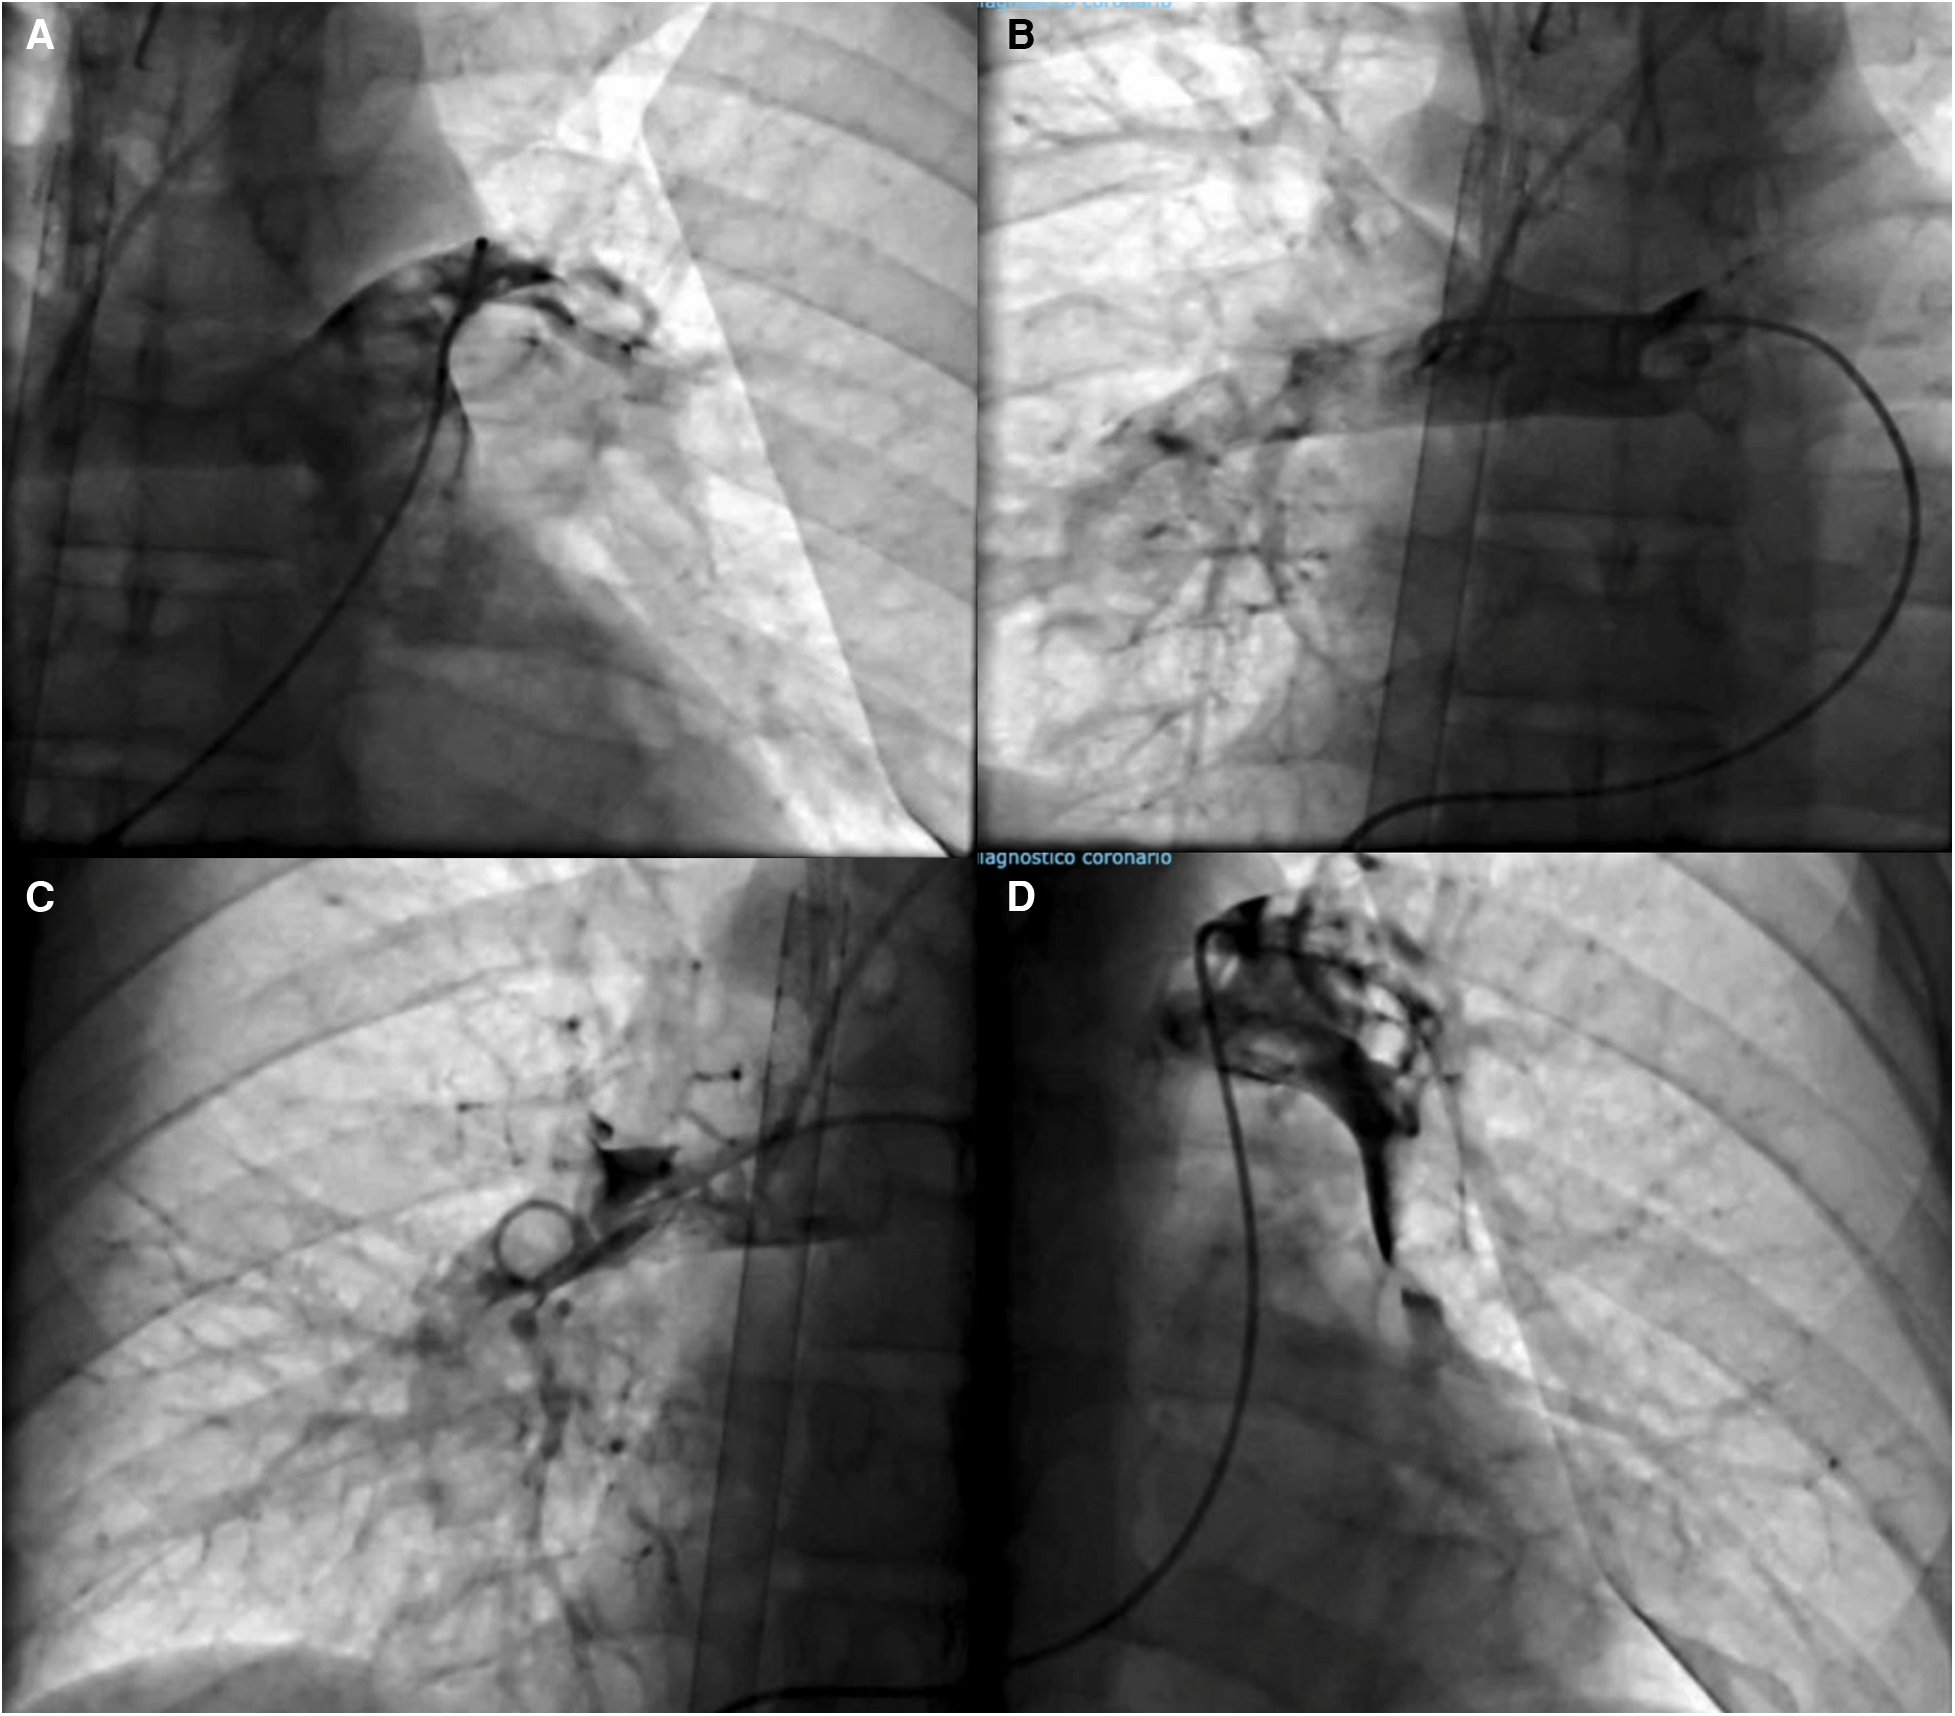

The patient was subsequently transferred to the catheter lab. We used a left femoral approach employing a 6 French pigtail catheter. Pulmonary angiography showed a high thrombus burden in both principal pulmonary arteries (Figure 2). We initiated a pharmaco-invasive approach involving manual mechanical fragmentation followed by catheter-directed thrombolysis using 5 mg of alteplase in each pulmonary artery, markedly improving pulmonary circulation (Figure 2). Coronary angiography excluded obstructive coronary disease. After successful pharmaco-invasive therapy, the patient was admitted to the ICU. On the following day, the patient remained under VA-ECMO support, requiring vasopressor infusion with norepinephrine, vasopressin, and milrinone due to hemodynamic instability and low pulsatility. A transthoracic echocardiogram showed right ventricular dilatation (43 mm), mild global hypokinesis, reduced biventricular systolic function with a left ventricular ejection fraction (LVEF) of 46%, and tricuspid annular plane systolic excursion (TAPSE) of 14 mm. Follow-up laboratories showed DD 140,404 mcg/ml, hs-c-TnI 26,675 ng/L, BNP 32.6 pg/ml, pH 7.33, PCO2 55 mmHg, and lactate 9.4 mmol/L (Figure 3). On the third day, creatinine levels increased to 2.8 mg/dl, along with a decreased urine output, prompting the initiation of continuous renal replacement therapy.

Figure 2

(A, B) Pulmonary angiography shows a filling defect in both principal pulmonary arteries. (C, D) Final angiography showing improved pulmonary circulation after pharmacoinvasive treatment.